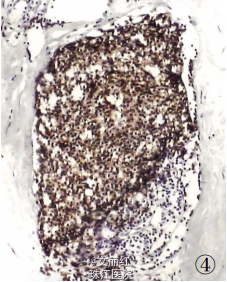

请糖尿病科会诊后,将血糖控制稳定后行肿物切除术。术中见肿物大小12*8*6cm,无包膜,切面实性,大部分为灰白色,质地硬。予以完整切除。冰冻提示良性病变。术后镜检:乳腺间质中含致密的胶原纤维似瘢痕样,小叶及导管周围件较多炎细胞浸润。病理诊断:糖尿病性乳腺病。

糖尿病性乳腺病是胰岛素依赖型糖尿病的一种罕见并发症,多件于绝经前女性。该病外科检查可触及乳腺内不规则肿物,边界不清,质硬,无痛且活动度差,X线提示病变区密度增加。超声显示低回声实体组织。以上表现与乳腺癌难以区分,然而两者治疗完全不同,如何鉴别、避免漏诊、误诊成为治疗关键。